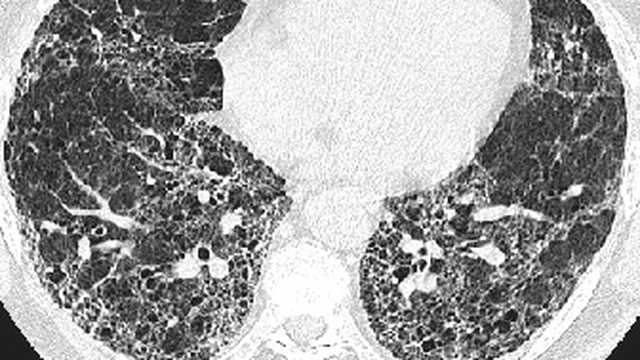

Xơ phổi 1/3 là tình trạng bệnh lý khá nguy hiểm, đặc biệt nghiêm trọng nếu không được phát hiện và điều trị sớm. Tuy nhiên, thực tế cho thấy, không phải ai cũng biết xơ phổi 1/3 là gì? Bài viết hôm nay của Nhà thuốc Long Châu sẽ giúp bạn đọc hiểu rõ hơn về tình trạng bệnh lý này.